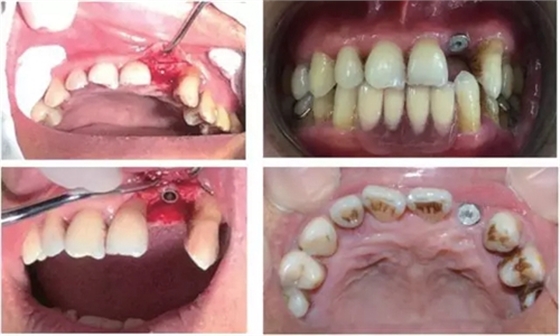

行影像學(xué)檢查(圖2);種植一枚Zuga 3.5*10 mm種植體,扭力≥35 N•cm,旋入愈合基臺(tái)(healing abutment)(圖3、4)。

圖3 22種植術(shù)前后照片

圖4 種植術(shù)后影像學(xué)檢查

3個(gè)月后,分別使用傳統(tǒng)的轉(zhuǎn)移桿硅橡膠取模以及口內(nèi)掃描取模進(jìn)行修復(fù)(圖5~8)。